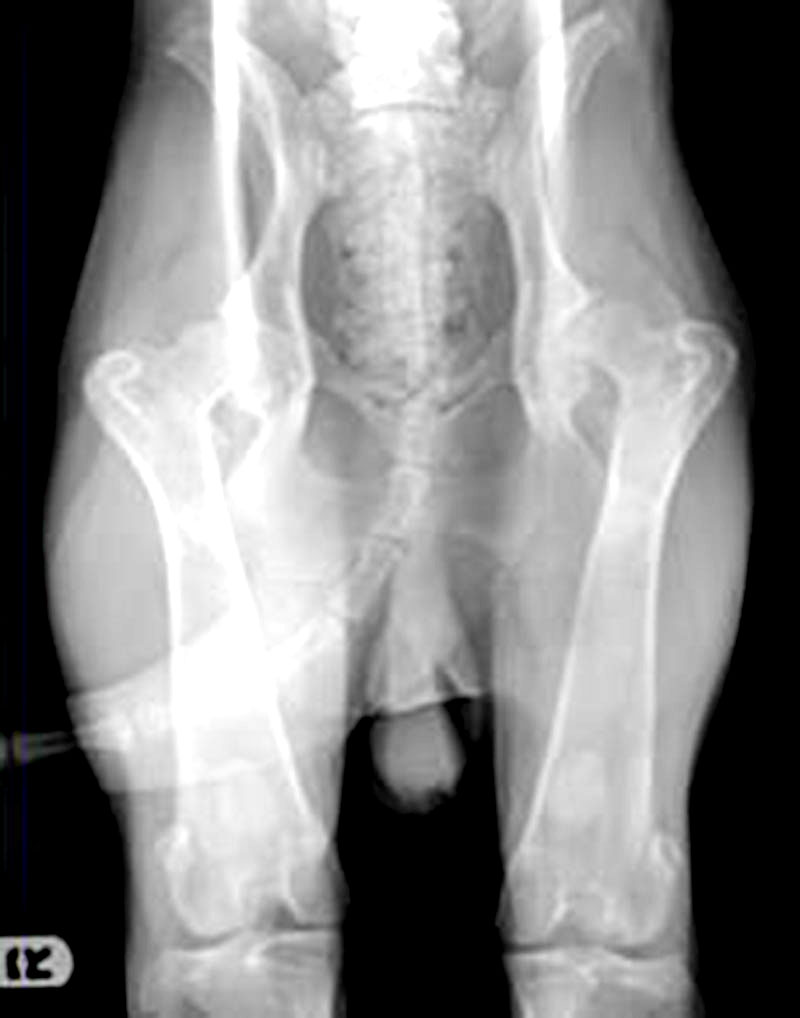

This is a dreaded disease that is complex (polygenic). It involves a malformation and hip joint laxity which occurs in many small and large breeds and has a complex mode of Inheritance (polygenetic). One of the first steps used in controlling this disease is a radiograph at two years of age, submitted to the OFA prior to breeding. Another tool used in the control of HD, is Penn HIP, where compressed and distracted hip radiographs are compared, and a distraction index (DI) is formulated. This method quantifies the amount of laxity of the soft tissues of the hip joint. For complex or polygenetic disorders such as HD the preferred method of control when no genetic test available involves the use of breadth and depth of pedigree which means the study of the breeding partners, their littermates and those of their parents and grandparents for three generations. The risk for producing HD has been shown to depend on the frequency with which the disorder occurs among the littermates and close relatives.

Radiograph of young male dog

Skeletal view of hip socket